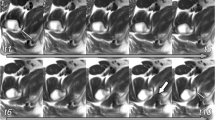

Radiographic setup

All stereoradiographs were recorded using a dynamic RSA system (Adora RSAd, NRT X-Ray, Denmark). Sampling frequency was five frames/s, pulse width 16 ms. Roentgen tubes were positioned with a 45° cranio-caudal- and 20° medio-lateral tilt directed at the hip joint from the cranial-caudal direction. Beneath the table a uniplanar calibration box (Box 14; Medis Specials, Leiden, the Netherlands) was placed in a 45° angle to the horizontal plane (Fig. 1). The two image detectors (Canon CXDI-50RF) were slotted in the calibration box. Source image distance (SID) was 2220 mm and focus skin distance (FSD) 1140 mm. Exposure settings for dRSA recordings were 130 kV, 500 mA, 16 ms and resolution was 1104x1344 pixels (79 DPI).

Preoperatively the cadaver specimens were CT-scanned and dRSA was performed. One dynamic RSA recording of the hip during FADIR motion, which is the movement of the donor leg from full extension through flexion aiming at 90°, adduction to stop, and internal rotation to stop (end range) was made (Fig. 1). The FADIR motion was performed slowly due to low frame rate and to ensure a controlled motion. ACH was performed by the senior surgeon (BMK). Postoperatively dRSA was repeated and a postoperative CT-scan of each specimen was performed.

Analysis of radiographs

For analysis of radiographs the commercially available software model-based RSA 4.01 (RSAcore, LUMC, Leiden, The Netherlands) was used. For each specimen calibration of the image was performed in the first frame. For the mbRSA-analysis the created bone models were implemented in the software program. Contours of the pelvic- and femur bones were detected on the two simultaneous images of the same scene by the Canny Edge Detector and relevant contours were manually identified, aiming to use similar contours in each frame (Kaptein et al. 2004). The software automatically positions the bone models using three consecutive algorithms: IIPM, DIFDHSAnn and DIFDoNLP. These algorithms estimate the pose by minimizing error between the virtual projections of the bone models and the manually detected contours on the radiographs (Kaptein et al. 2004). For each specimen the frame in the sequence, in which the hip was in end range FADIR, was identified and used to determine flexion, adduction and rotation angles of the hip joint (calculated according to the ISB recommendation (Wu et al. 2002) along with femoral end-range subluxation (the norm (T2 = X 2 + Y2 + Z2) of translations of the femur bones’ center of rotation with respect to the pelvis). The translation was the difference in position of the center of the femur between two frames in the femur coordinate system.

Precision of mbRSA